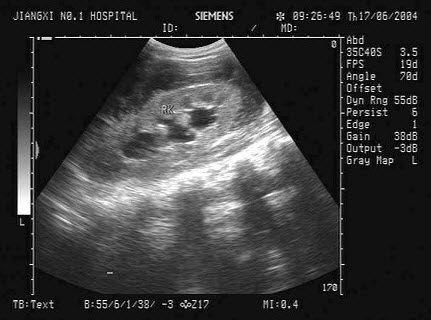

65、单项选择题

结合超声图像,该病例肾结石为哪一部位()

A.下极肾盏

B.中极肾盏

C.上极肾盏

D.肾门

E.肾乳头处